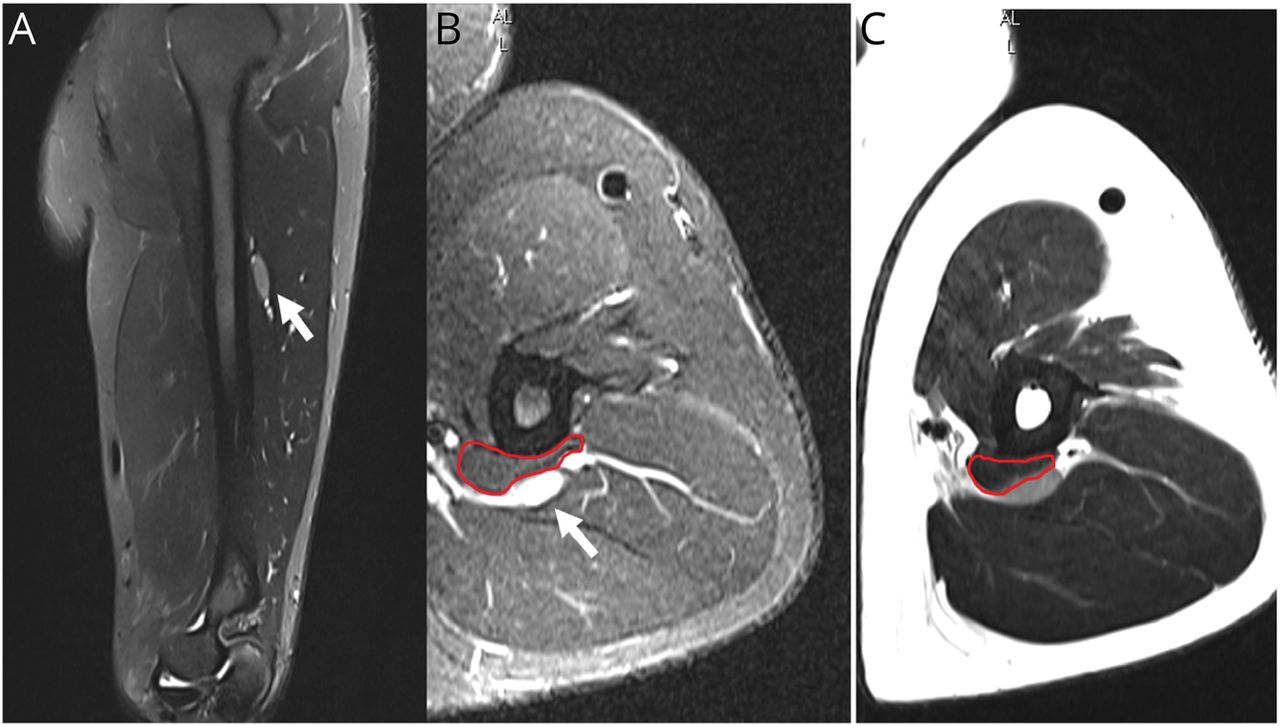

左桡神经(沃特。)超声波(A)。沃特。(星号)增加了回声,在中间三分之一的肱骨横截面积;肱三头肌的辅助腹部肌肉(点)。手术减压pre-R.n。释放(B)和post-R.n。释放(C)证实了这一圈套病因。